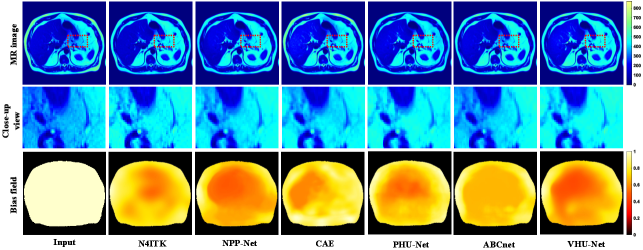

Refer to caption

Figure 9: The qualitative comparison on real T2-weighted PanSegData. From top to bottom, the rows show the corrected MRI images, the zoomed-in local views, and the estimated bias fields.

4.6.2 Qualitative Comparison

Fig. 9 illustrates the qualitative performance of various bias field correction methods on the T2-weighted abdominal dataset. The uncorrected input image exhibits visible intensity inhomogeneities, especially around the organ boundaries, which compromise tissue contrast and anatomical interpretability. N4ITK, NPP-Net, CAE, ABCnet, and PHU-Net produce smooth bias fields and enhance intensity uniformity. However, these methods still leave residual artifacts or compromise anatomical detail, as shown in the full and zoomed-in views. In comparison, the proposed VHU-Net demonstrates the best overall performance. The corrected images exhibit high intensity homogeneity, enhanced tissue contrast, and well-preserved anatomical details. Notably, the estimated bias field is smooth, spatially coherent, and consistent with expected low-frequency characteristics. These qualitative observations suggest that VHU-Net exhibits robust performance on real clinical data.

Figure 10: The qualitative comparison on real T1-weighted PanSegData. From top to bottom, the rows show the corrected MRI images, the zoomed-in local views, and the estimated bias fields.

Fig. 10 presents the qualitative comparison of different bias field correction methods on the real T1-weighted PanSegData. The original MR image exhibits pronounced intensity inhomogeneity, particularly in peripheral regions. The result obtained by N4ITK appears visually similar to the uncorrected input, indicating that the correction was largely ineffective. This failure stems from the fact that N4ITK assumes intensity uniformity across distinct tissue types. However, this assumption does not hold for T1-weighted abdominal MRI, where complex anatomical structures and heterogeneous tissue compositions cause substantial natural intensity variations. Consequently, N4ITK struggles to distinguish between genuine anatomical contrast and bias-related shading, leading to under-correction. Other learning-based methods demonstrate more effective bias removal and yield improved visual homogeneity. Nevertheless, their corrected images still show local intensity inconsistencies, especially in regions with strong field distortion, as illustrated in the close-up view. In contrast, the proposed VHU-Net provides the most visually consistent result, producing spatially coherent bias field estimates while preserving anatomical detail. These observations suggest that VHU-Net better adapts to the complex signal distribution of real abdominal MR images, effectively separating bias artifacts from inherent tissue contrast.

Figure 11: The qualitative comparison on prostate dataset. From top to bottom, the rows show the corrected MRI images, the zoomed-in local views, and the estimated bias fields.

4.7.2 Qualitative Comparison

Fig. 11 provides a comparative visualization of bias field correction performance across several representative methods on real prostate MRI images. While NPP-Net, CAE, ABCnet, and PHU-Net generally generate smooth bias fields, they exhibit insufficient compensation near the margins, leaving edge-related artifacts unaddressed. N4ITK demonstrates strong global bias correction capabilities. however, it tends to over-brighten the region above the prostate, resulting in the loss of fine anatomical details. The proposed VHU-Net addresses these challenges effectively. The restored image exhibits improved uniformity and structural detail, without introducing over-smoothing or noise artifacts. Besides, it produces a bias field that is both smooth and anatomically consistent.